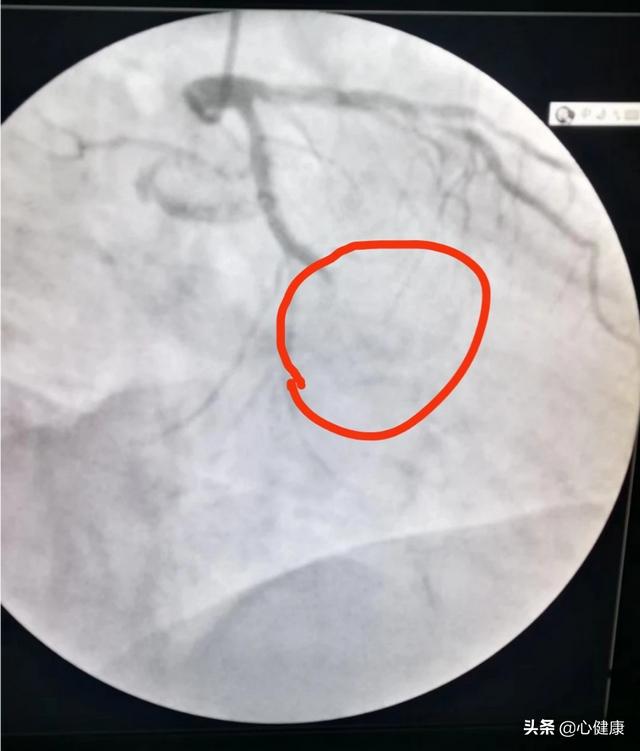

2、重大な病変の存在、例えば、最初の画像診断で、70-80%程度の狭窄があり、ステントを留置するかしないかを決定し、最終的にステントを留置しないことを決定した後、1年後に、状況に応じて画像診断を再検査し、進展があるかどうかを確認することができる。

2.ステントを留置していない血管に残存する重要病変の70%の狭窄(ステント留置の有無にかかわらず);

ステント業界や手術手技の進歩にもかかわらず、ステントの再狭窄率は依然として約5%である(以前は約20%であった)。このような患者は再狭窄のリスクが高いため、術後6〜9ヵ月後または1年後にフォローアップの画像診断を受けるように外科医から指示されることが多い。その主な目的は、1.ステントの状況を明らかにすること、ステント内増殖や再狭窄があるかどうか、2.未治療のまま残っている重症病変がさらに増悪を示すかどうか、増悪がある場合はそれに間に合うように対処し、まだ生命を脅かすほどではない心筋梗塞を回避すること、である!